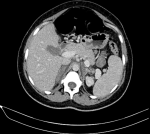

Diagnostic assessment: initial abdominal ultrasound excluded surgical emergencies such as acute appendicitis, cholecystitis, or placental abruption. Urinalysis showed leukocyturia (20 cells/field) and hematuria (10 cells/field) without visible microorganisms; subsequent urine culture remained negative. Based on fever, lumbar tenderness, and leukocyturia, a diagnosis of acute pyelonephritis was suspected, and empirical cefotaxime was initiated. However, the lack of clinical improvement after 48 hours, persistent fever, intractable vomiting, and onset of tachypnea (46 breaths/min) prompted diagnostic reconsideration. Laboratory investigations demonstrated a marked inflammatory response (C-reactive protein 266 mg/L). Arterial blood gas analysis revealed metabolic acidosis (pH 7.33, PaCO2 11 mmHg, HCO3- 11 mmol/L) without hyperlactatemia (lactate 1.6 mmol/L). Serum electrolytes showed hyponatremia (129 mmol/L) and hypokalemia (3.2 mmol/L), with preserved renal function. Given the acute tachypnea, pulmonary embolism was suspected, and CT pulmonary angiography was performed, excluding this diagnosis. Alternative diagnoses were systematically considered and ruled out, including appendicitis, cholecystitis, pancreatitis, renal infarction, adrenal hemorrhage, Hemolysis elevated liver enzymes and low platelets (HELLP) syndrome, and acute fatty liver of pregnancy. Because magnetic resonance imaging (MRI) was not emergently available at our institution and given the persistence of unexplained symptoms, contrast-enhanced abdominal CT was performed, revealing bilateral adrenal enlargement without contrast enhancement (Figure 1, Figure 2). Both adrenal glands appeared enlarged with no parenchymal enhancement after intravenous contrast administration, consistent with adrenal ischemia and infarction. The coronal reconstruction confirmed the bilateral and symmetrical nature of adrenal involvement. Dotted lines on imaging highlighted the non-enhancing adrenal glands. Endocrine evaluation showed a serum cortisol level of 128.2 nmol/L, which is below the threshold suggestive of adrenal insufficiency in critically ill patients according to current guidelines. Adrenocorticotropic hormone (ACTH) measurement and dynamic testing were not immediately available and were not performed to avoid delaying urgent treatment.

Figure 1: axial view of contrast-enhanced abdominopelvic computed tomography (CT) showing bilateral adrenal enlargement with lack of contrast enhancement in a 34-week pregnant patient with bilateral adrenal infarction